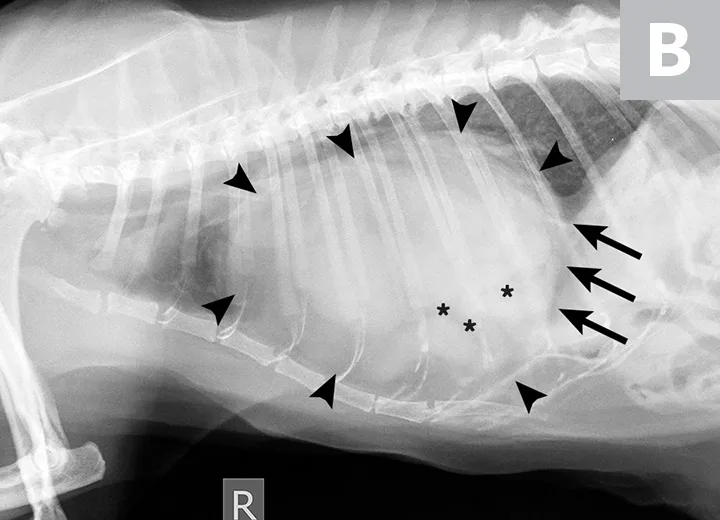

Two-view thoracic radiographs (Figure 1) were obtained with Joker under mild sedation (butorphanol [0.2 mg/kg IV]). Marked widening of the cardiac silhouette, both in height and width, with loss of delineation of the caudal cardiac margin, was observed. Superimposition of air tubular opacities to the cardiac silhouette were also noted. The liver was not visible at its physiologic position in the cranial abdomen. Considering these radiographic findings, a presumptive diagnosis of peritoneopericardial diaphragmatic hernia (PPDH) was made.

Ventrodorsal (A) and lateral (B) thoracic radiographs demonstrating an enlarged cardiac silhouette (arrowheads) with gas-filled tubular opacities consistent with the GI tract (asterisks) and loss of the caudal cardiac margin (arrows)